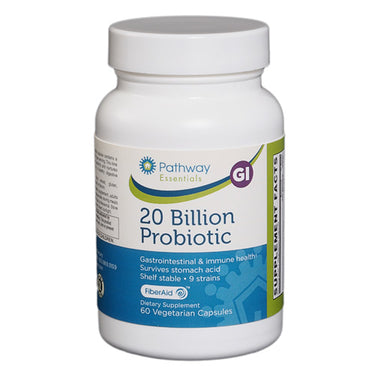

Why should I choose Pathway supplements?

MORE SUPPLEMENTS FOR A HEALTHIER YOU